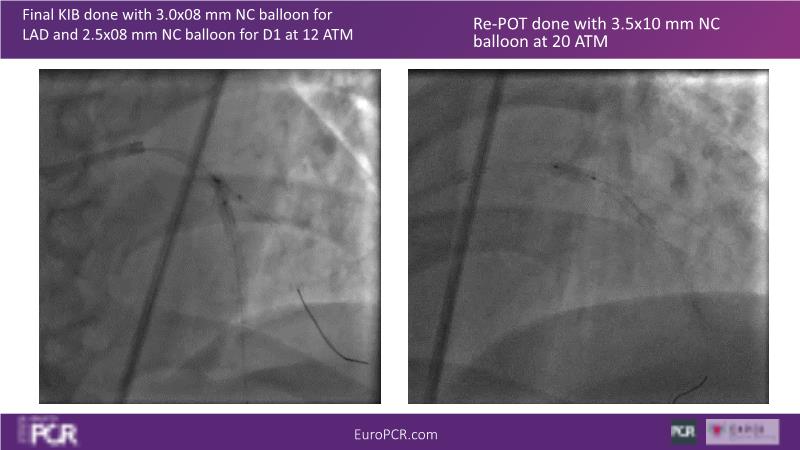

Watch this session on PCI in diabetic patients to learn about a groundbreaking technology addressing the complexities of this critical subgroup. Discover the next-generation DES and DCB stent platform and the innovative Envisolution technology behind it. Understand how it works, its advantages in managing complex cases, and what sets it apart from other technologies. Gain insights into the future of polymer-free DES + DCB stent technology and its potential impact on patient care.